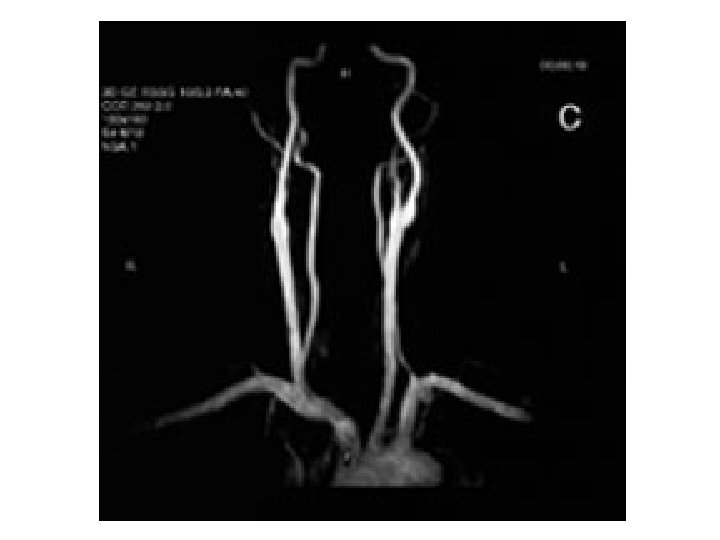

Atherosclerosis(AL) Atherosclerosis • AT is clinically silent until critical stenosis / thrombosis / aneurysma/ emboly occurs • insufficient supply of peripheral tissue – intermitent claudication, angina pectoris – sudden closure: AIM, CMP diagnosis: angiography, ultrasound examination therapy: risk factors, LDL (statins)

CT and MR